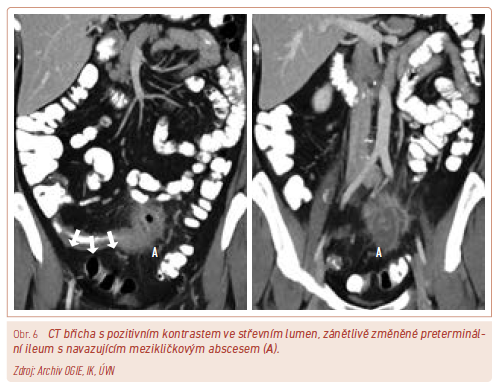

Výpočetní tomografie

Výpočetní tomografie (CT) je dnes plně dostupnou metodou využívanou k zobrazení dutiny břišní po předchozí aplikaci kontrastní látky perorálně a intravenózně. Typ a způsob aplikace kontrastní látky se liší podle toho, co chceme provedeným vyšetřením zjistit. K posouzení rozsahu zánětlivého postižení střeva nejčastěji provádíme CT enterografii. Při suspekci na komplikace CN, jako jsou tekutinové kolekce, abscesy, píštěle, dehiscence anastomóz, indikujeme CT břicha s kontrastní látkou perorálně a intravenózně aplikovanou (obr. 6).

Vyšetření pomocí CT slouží také jako metoda terapeutická, která umožňuje intervenční léčbu v podobě drenáže tekutinových kolekcí. Přes veškeré benefity, které CT vyšetření přináší, je třeba mít na paměti radiační zátěž, kvůli níž v současnosti preferujeme vyšetření střeva magnetickou rezonancí (MR).